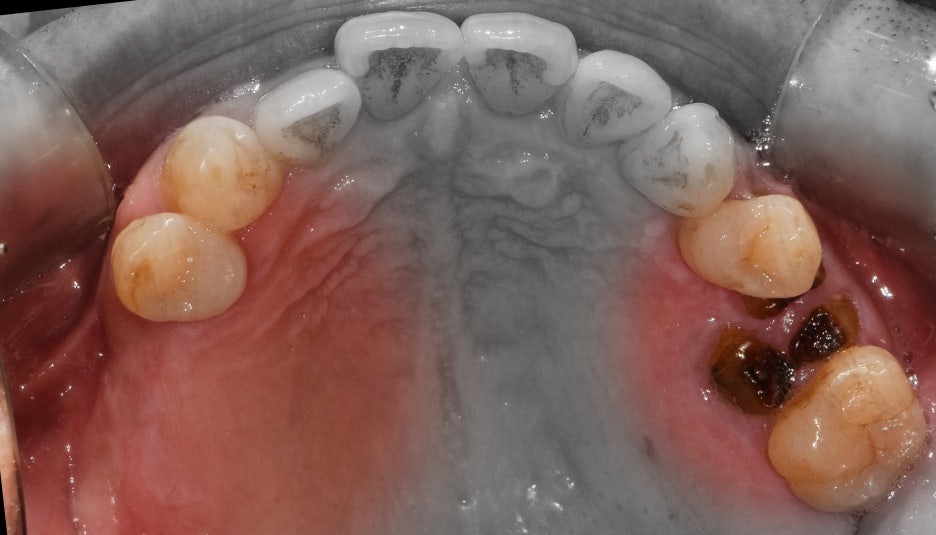

저를 찾아오셨던 이 분은, 이미 치아들이 많이 결손이 된 상태로 오셨었습니다.

한 쪽에는 뿌리만 남아있는 치아, 그리고 다른 곳에는 아예 치아들이 없는 상태입니다.

맞물리는 치아들은 앞니밖에 없는데 앞니로는 고기를 뜯거나, 질긴 음식을 드실 수 없죠.

즉, 교합 관계 불량에 따라서 올바른 저작 활동을 하실 수 없는 상태로 판단 되었었습니다.

그래서, 먼저 제 기능을 하지 못하며 염증만 가득 품고 있는 일부 치아들을 발치했습니다.